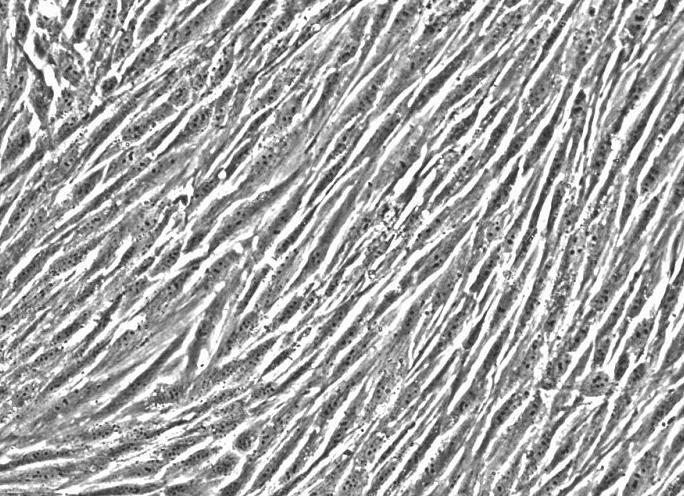

大鼠主动脉平滑肌细胞/大鼠主动脉平滑肌细胞/大鼠主动脉平滑肌细胞

RASMC大鼠主动脉平滑肌细胞|RASMC细胞|大鼠主动脉平滑肌细胞|RASMC细胞|大鼠主动脉平滑肌细胞

大鼠主动脉平滑肌/主动脉平滑肌/主动脉平滑肌细胞

【原代细胞】大鼠主动脉平滑肌/主动脉平滑肌/主动脉平滑肌细胞

大鼠主动脉平滑肌细胞